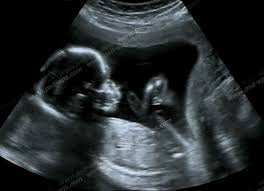

• مراقبت و پایش روزانه مادران باردار، سلامت مادر و جنین، شناسایی مشکلات احتمالی، رسیدگی به بارداری پرخطر و حمایت روانی حفظ سلامت نسل آینده را تضمین می‌کند.

به گزارش خبرنگار گروه اجتماعی پایگاه خبری تحلیلی «صبح هامون»، بارداری تجربه‌ای حساس است که نیازمند مراقبت مداوم برای سلامت مادر و جنین است. مادرانی که برای اولین‌بار باردار می‌شوند یا فرزند اول خود را انتظار دارند، با چالش‌های ویژه‌ای روبه‌رو هستند. پایش روزانه قند خون، فشارخون، وزن و وضعیت رشد جنین از اصلی‌ترین اقدامات پیشگیری از عوارض است. این مراقبت‌ها مشکلات احتمالی را در مراحل اولیه شناسایی می‌کند.

مادران باسابقه بیماری‌های زمینه‌ای مانند دیابت یا فشارخون بالا، بیشتر در معرض زایمان پرخطر قرار دارند. انجام مرتب آزمایش‌ها، سونوگرافی و مشاوره با متخصص، امکان شناسایی زودهنگام مشکلات را فراهم می‌کند. پایش دقیق وضعیت جسمی اعتماد مادر را افزایش می‌دهد و او را برای مواجهه با دوران بارداری و زایمان آماده می‌کند.

کارشناس مامایی ادامه داد: پایش سلامت جنین اهمیت حیاتی دارد و شاخص‌های اصلی آن رشد، ضربان قلب، وضعیت قرارگیری و حرکات جنین است. بررسی‌های منظم این شاخص‌ها مشکلاتی مانند رشد کند، اختلالات قلبی و ناهنجاری‌های ساختاری را به‌موقع مشخص و امکان مراقبت پیش از تولد را فراهم می‌کند.